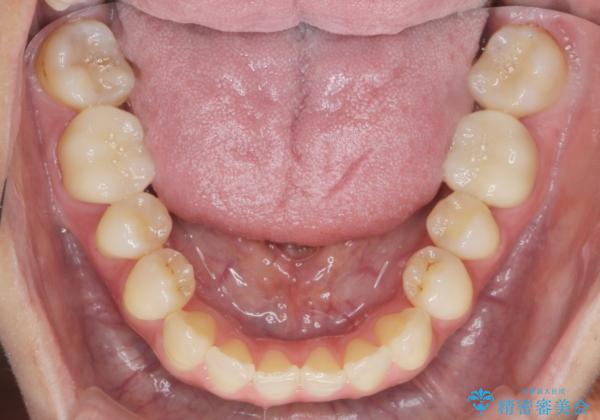

- 30代女性

- 口の中に見える銀歯を、金属アレルギーの対策と審美性の向上のため全て除去したい!と希望され来院されました。

銀歯を丁寧に除去したのち、精度の良いセラミックインレー、セラミッククラウンで修復・補綴処置を行っていきます。